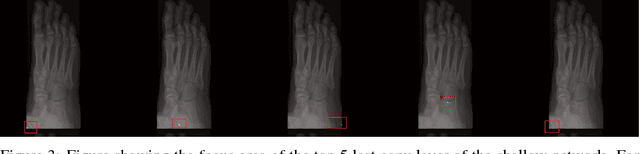

Abstract:One of the main challenges for broad adoption of deep learning based models such as convolutional neural networks (CNN), is the lack of understanding of their decisions. In many applications, a simpler, less capable model that can be easily understood is favorable to a black-box model that has superior performance. In this paper, we present an approach for designing CNNs based on visualization of the internal activations of the model. We visualize the model's response through attentive response maps obtained using a fractional stride convolution technique and compare the results with known imaging landmarks from the medical literature. We show that sufficiently deep and capable models can be successfully trained to use the same medical landmarks a human expert would use. Our approach allows for communicating the model decision process well, but also offers insight towards detecting biases.